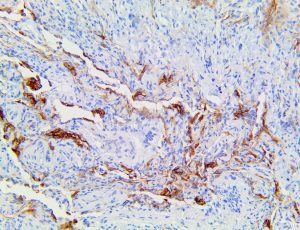

It is the ICU physician who is most likely to witness one of the deadliest manifestations of the abnormal immunological response, the cytokine storm syndrome (CSS). This response is also referred to by some as the cytokine release syndrome (CRS). CSS is characterized by continuous activation and expansion of macrophage and lymphocyte populations, which secrete large amounts of cytokines, causing the cytokine storm. This massive cytokine release is akin to hemophagocytic lymphohistiocytosis (HLH) disease, a syndrome characterized by initial unchecked and persistent activation of cytotoxic T lymphocytes and NK cells.

Clinical and laboratory manifestations of HLH include fever, enlarged liver and/or spleen, neurologic dysfunction, coagulopathy, liver dysfunction, cytopenias (i.e., low levels of erythrocytes, leukocytes, and/or platelets), hypertriglyceridemia, hyperferritinemia, hemophagocytosis, and eventually diminished NK cell activity as the immune system becomes progressively paralyzed. HLH can be familial (primary HLH) or secondary to another disease process (sHLH), such as rheumatic disease, in which it is referred to as macrophage activation syndrome (MAS, characterized by elevated ferritin).